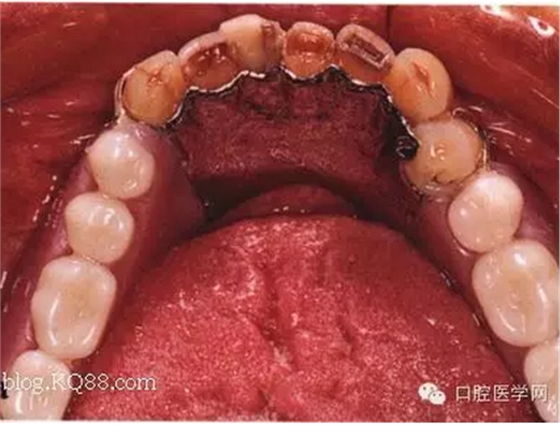

先注明一下:本文圖片部分來自李望松的支架設(shè)計圖譜收集u/210/archives/2008/25181.html,借圖表達一下,沒有別的目的,只是讓文章更生動些,李老師一直是我崇拜的偶像,只是近來很少見到他的文章,期待李老師的大作,言歸正傳——————修復(fù)大夫要精通支架設(shè)計,作為一個修復(fù)大夫,是第一個獲得患者牙體狀況的,所以說在哪放個合支拖,在哪放個卡換,至關(guān)重要,因為我們做的是個有創(chuàng)不可逆操作,既要兼顧牙周狀況,又要兼顧粘膜狀況,以及牙槽脊的情況,所以說當給患者做完檢查以后我們頭腦中就應(yīng)該有一個大體支架了,以前,總是太依賴加工廠了,取完模剩下的好像都是交給了加工廠了,怎么設(shè)計,你看摸著辦吧,仿佛設(shè)計那是加工廠的事,可是做了幾回再加上自己的學(xué)習(xí),經(jīng)驗,加工廠的設(shè)計總是不怎么樣,以前設(shè)計的方案仿佛根深蒂固,一直就認為那是正確的就那么設(shè)計,再加上以前看過支抗兄的一篇文章,也是深有感觸,一個不科學(xué)的設(shè)計方案,那樣就成了一個慢性拔牙器??纯磶追鶊D片

看紅箭頭處為什么要空出一點距離?,看看自己加工廠設(shè)計的不管牙怎樣是不是都成了一個整體呢?對于愕板或者是

愕桿要離開齦緣4-6mm,以促進食物對牙齦的按摩沖刷作用,促進牙齦健康

前愕桿要離開至少6mm如下圖

愕板的后部(顫動線處)要與黏膜輕接觸,以防義齒行使功能時產(chǎn)生壓痛